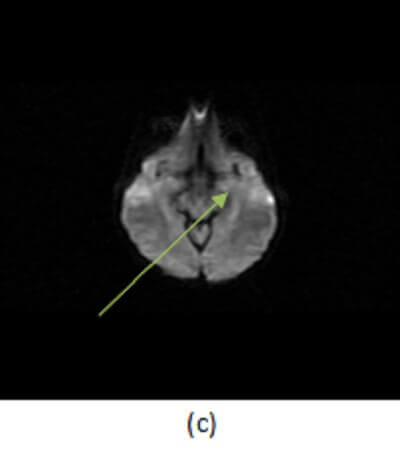

Figure 1: Increased (a,red arrow) FLAIR signal abnormality preferential for the left mesial temporal lobe is T1 hypointense (b, blue arrow ). It does not demonstrate restricted diffusion (c, green arrow) or enhance (not shown).

Understanding the imaging features of HSV encephalitis is important, since empiric antiviral therapy should be initiated if there is any suspicion for the condition. MRI is the most sensitive imaging modality. Imaging findings include T2/FLAIR signal abnormality involving the cortical and subcortical regions within the limbic system, especially the mesial temporal lobe. The findings are possibly bilateral but commonly asymmetric. There may be associated restricted diffusion on DWI and hemorrhage suggested by foci of decreased signal intensity on GRE sequences. Patchy or gyriform enhancement may be seen in these regions after contrast administration, or there may be no enhancement at all. The differential diagnosis also includes infarct and astrocytoma. A signal abnormality that lacks territorial restricted diffusion or that crosses vascular territories in a patient with sudden onset of symptoms and a suggestive LP help to differentiate HSV from infarct and tumor.